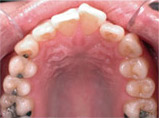

Before

Proceeding

After